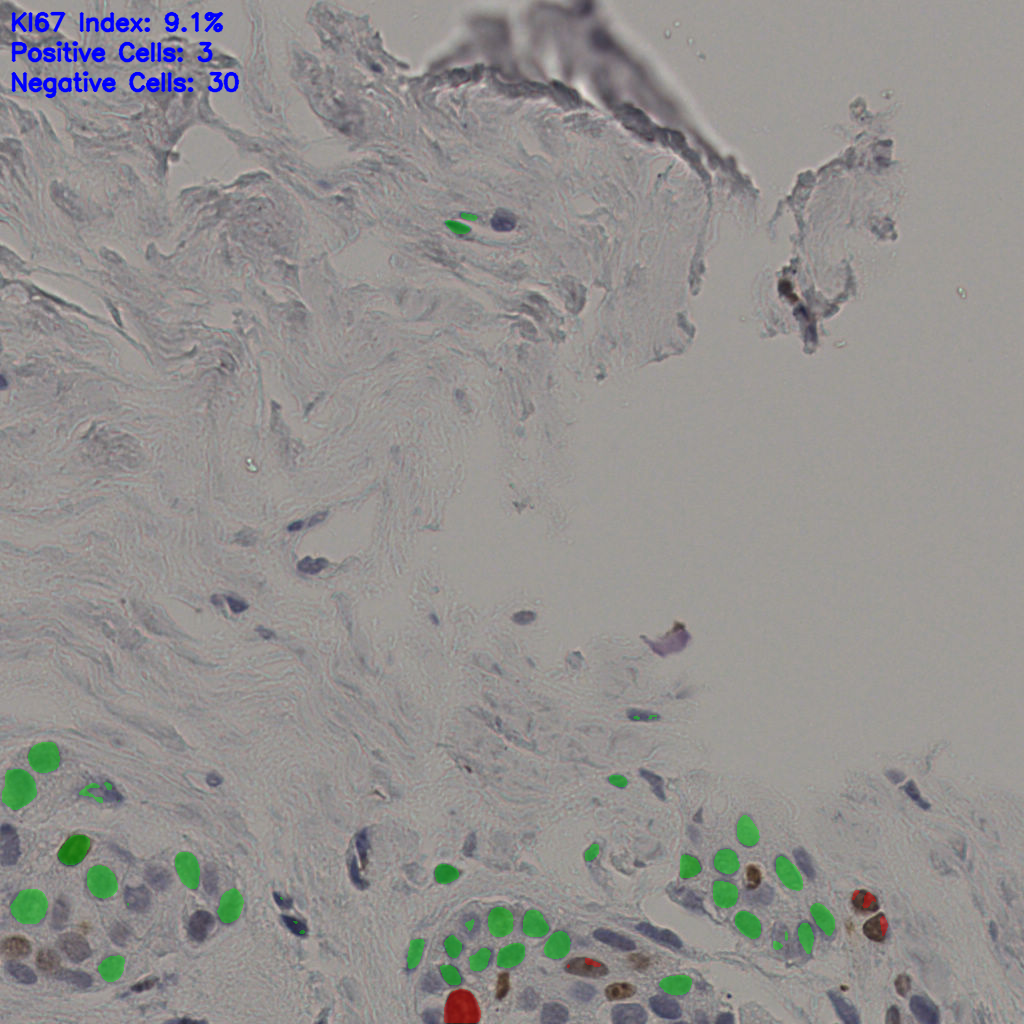

5.31%

Ki67 指数

阴 19502 阳 1093